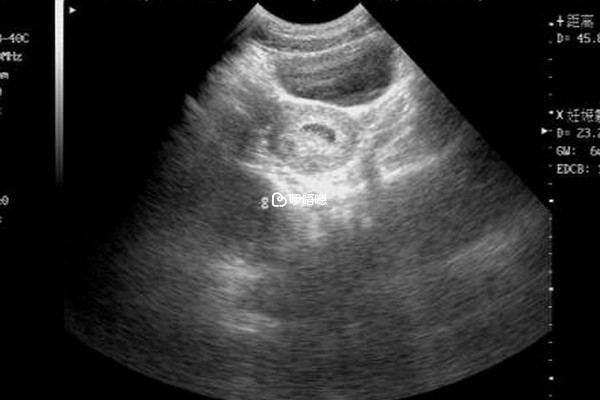

如果想要在試管移植之後避免囊胚著床在輸卵內,最好是在囊胚移植前進行雙側輸卵管切除手術或者雙側輸卵管結紮術,可以降低宮外孕的發生機率,另外,在移植囊胚之後還需要定期去醫院接受檢查,在移植四周到五週左右就可以利用B超檢查出是否存在宮外孕的可能。